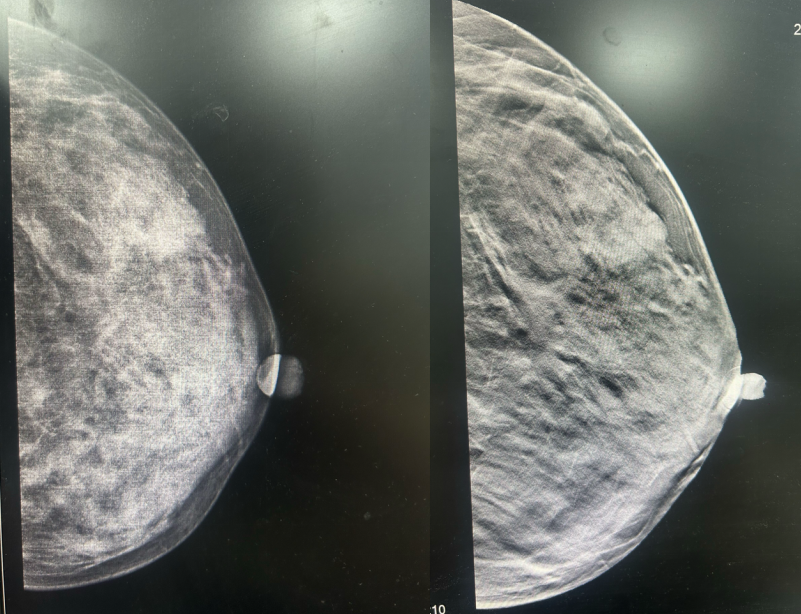

·乳腺DR

图3.2023年6月27日乳腺DR结果

1、左乳外下象限前中带肿块,恶性可能。(BI-RADS 4C)

2、右乳外上象限中后带局限性非对称致密,建议进一步检查。(BI-RADS 0)